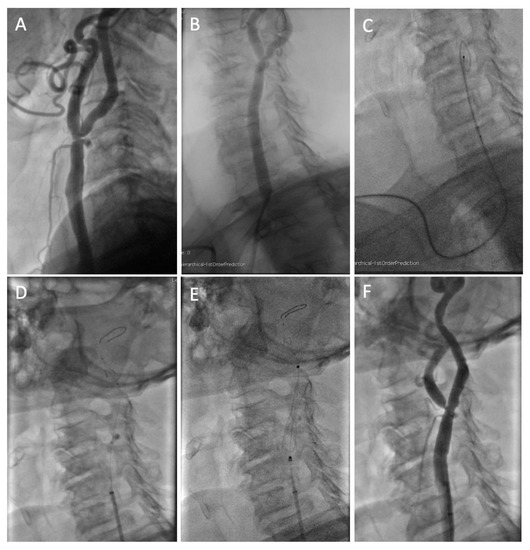

Carotid Artery Stenting Using Five-French Distal Radial Vascular Access

2.1. Interventional Procedure